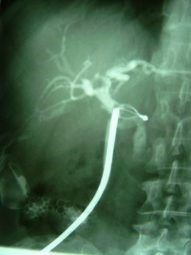

Extracción percutánea de cálculo de coledoco

Envíado por Dr. Carlos Miguel Zavaleta Consuegra